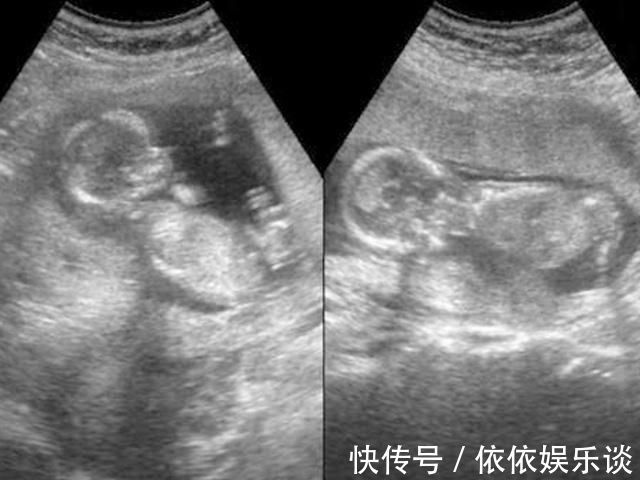

文章插图